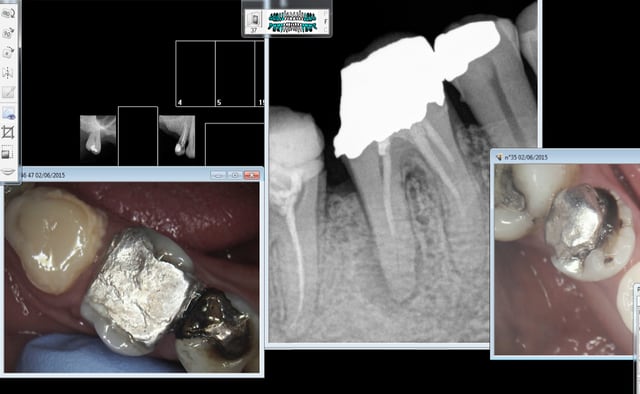

Mouahaha à l'instant patient qu'un confrère n'a pas eu le temps de prendre en urgence. -))))

C'est joli hein tous ces compos et amalgames de merde sur dents dévitalisées selon les données acquises de la science, hein ?-))))))

Alors rte ou pas rte, inlay core ou pas inlay core ? -))))